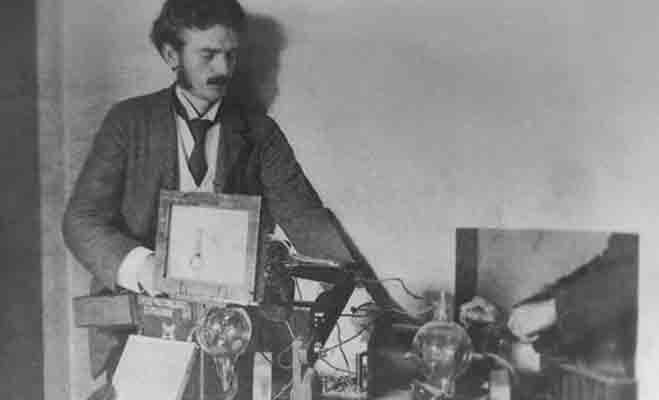

एक्स-रे विद्युत चुम्बकीय विकिरण का एक रूप है। इसकी खोज जर्मनी के एक सनकी भौतिक विज्ञानी विलहम रोएंटगन ने की थी। वह एक बार कैथोडिक रेज ट्यूब का अविष्कार कर रहे थ्ो। इस दौरान जब वह कैथोड किरणों के बंद होने पर कुछ लाइट चमक रही थी। उन लाइट की वजहों से वहां पर अपारदर्शी कवर के नीचे बिछा पेपर साफ दिख रहा है।

यह देख वह शॉक्ड हो गए और उन्होंने उन लाइट को अपने शरीर की ओर भी ट्राई किया। जिससे उनके शरीर की हड्डियां साफ दिखाई दे रही थीं। जिसके बाद इस वह दिशा में गहराई से सोचने लगे। उन्हें अहसास हो गया कि अगर इन एक्स-रे पर काम किया जाए तो कुछ नया हो सकता है। 1890 में वह इस मिशन में दिन रात काम करने लगे।

विलहम रोएंटगन नीदरलैंड में मास्ट्रिच विश्वविद्यालय के मेडिकल सेंटर में एक्स-रे पर कई शोध किए। लगातार प्रयास के बाद उन्हें 1895 में पहली बार इस दिशा में सफलता भी मिली। विलहम रोएंटगन ने कैथोड की किरणों के बुझने के बाद दिखने वाली इन लाइट्स को एक्स-रे नाम दिया था। इसके बाद उनका बनाया यह एक्सरे पूरी दुनिया में छा गया।

फिजिक्स के इस अविष्कार को 1901 में पहला नोबेल पुरस्कार मिला था। इसके बाद अब तक उनके अविष्कार किए गए एक्स-रे में काफी बदलावहो चुके हैं। समय के साथ आज एक्स-रे काफी डिजिटल होते जा रहे हैं। आज पूरी दुनिया में मनुष्य शरीर के आंतरिक हिस्सों में देखने के लिए एक्स-रे का इस्तेमाल किया जाता है।Interesting News inextlive from Interesting News Desk